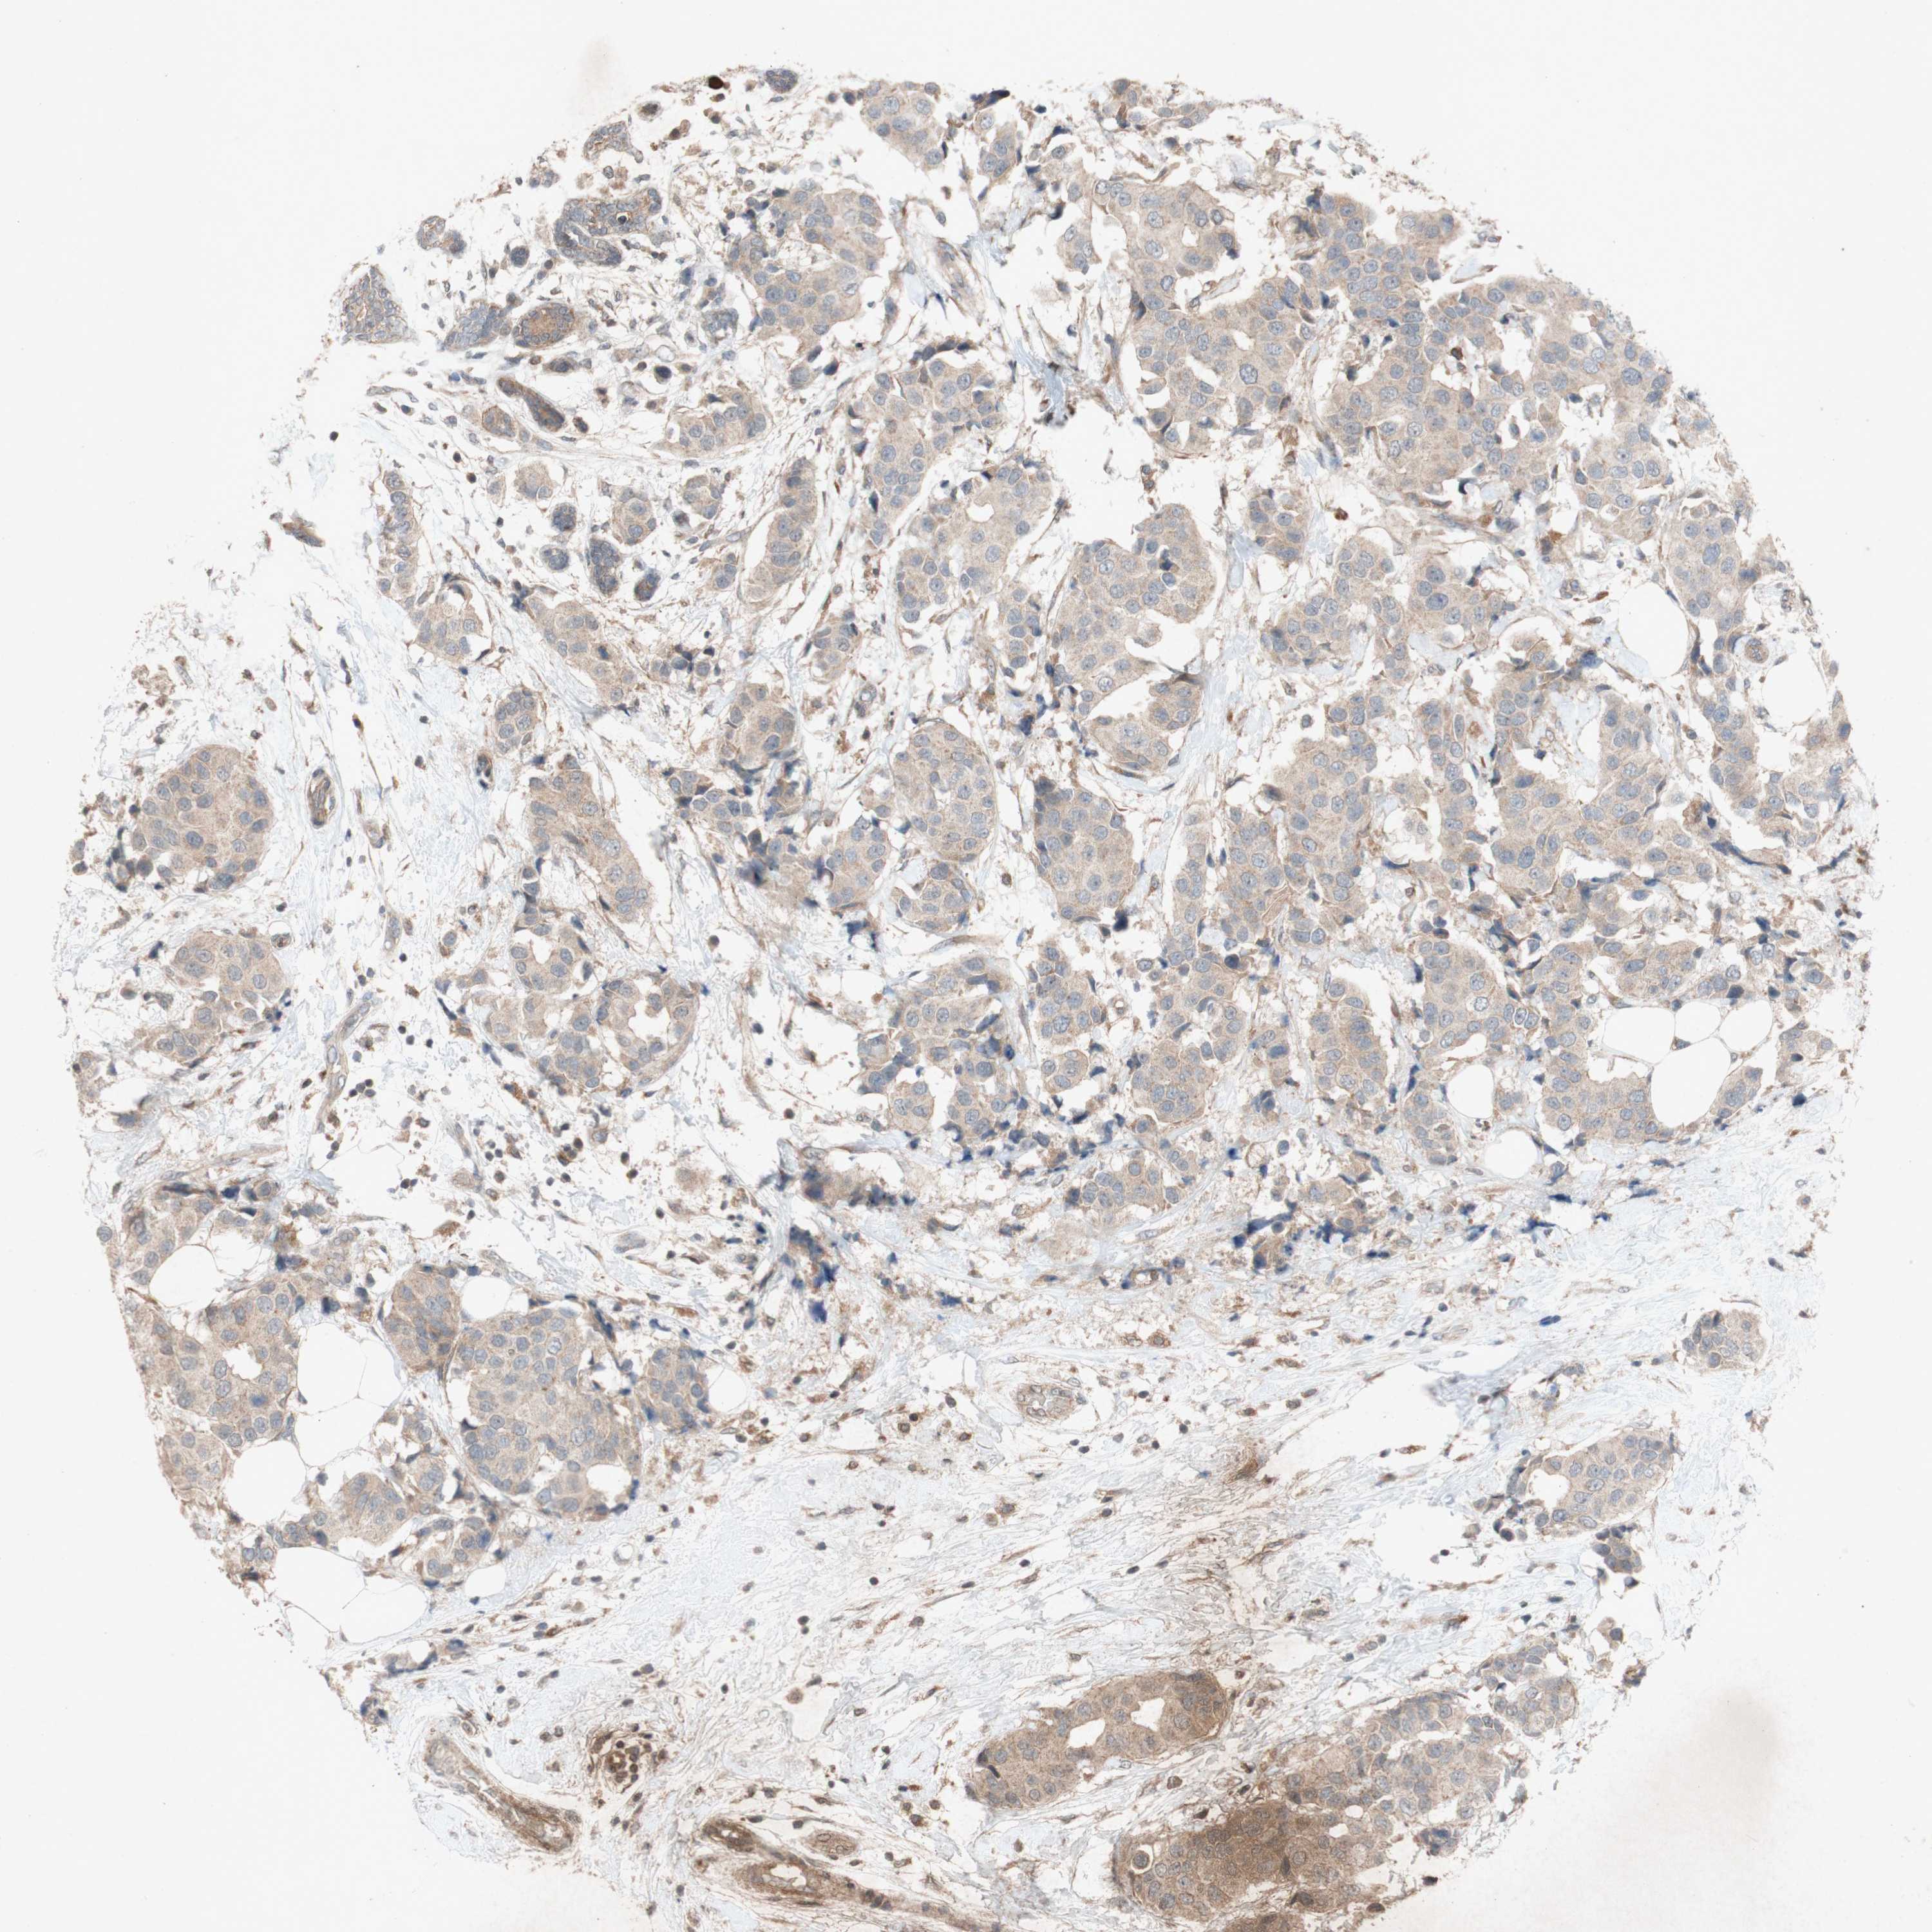

BRCA TCGA BRCA VALIDATION PROTEIN EXPRESSION

ANTIBODIES

AND

VALIDATION